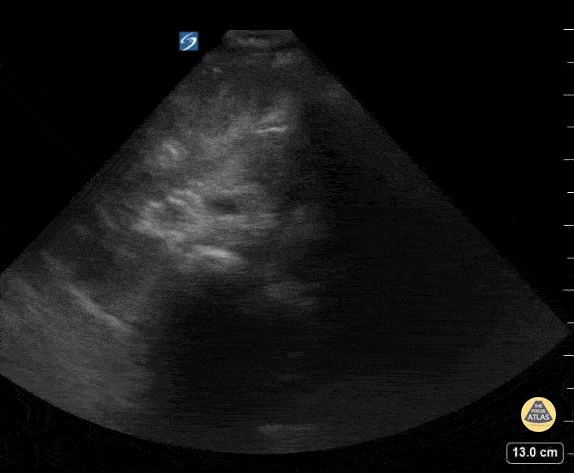

13 y/o M with abdominal pain. POCUS shows gallbladder sludge. Contributor: Kathryn Pade, MD, Rady Children's Hospital San Diego